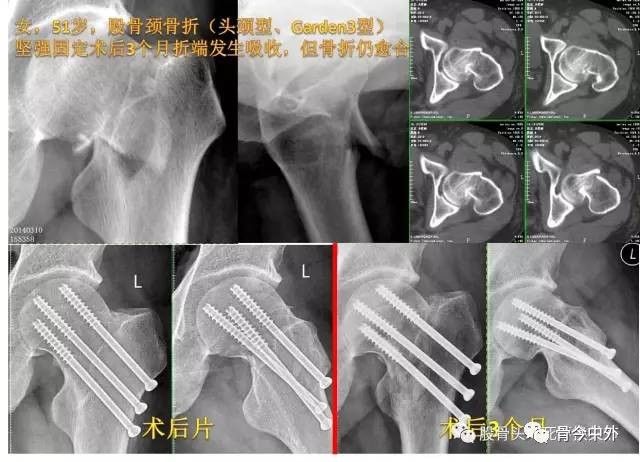

图8?三点三角形固定模式:三枚空心钉在空间呈三角形布局,钉体贴近股骨颈皮质,钉头达软骨下骨;坚强固定利于骨折愈合

图9?坚强固定利于骨折愈合,51岁女性术后3个月发生骨折端吸收、钉尾滑动,但并未影响骨折愈合

图10?男,52岁,股骨颈骨折坚强固定,有利于骨折愈合